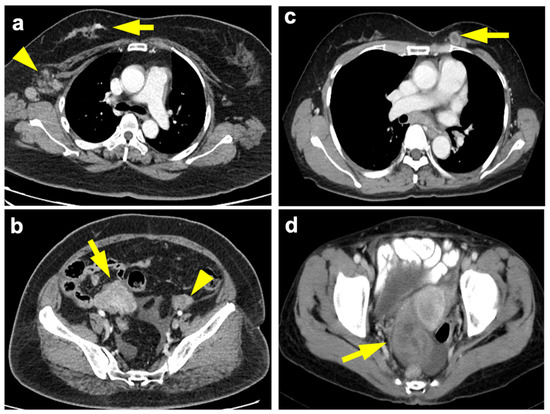

3.2. Malignant Ovarian Lesions

The 11 malignant ovarian lesions comprised primary ovarian epithelial cancer (n = 6), moderately differentiated Sertoli–Leydig cell tumor (n = 1), and metastasis from breast cancer (n = 4). Ovarian metastases from breast cancer originated from invasive ductal carcinoma (n = 2), lobular carcinoma (n = 1, Figure 2a,b) and angiosarcoma (n = 1). Their clinicopathological features are detailed in Table 2.

Figure 2.

(a) 54-year-old woman, breast invasive lobular carcinoma (T3N2aM1) with ovarian metastasis. Contrast-enhanced axial chest CT shows infiltrative tumor at the upper outer and upper inner quadrant of the right breast (arrow) with right axillary nodal metastases (arrowhead). (b) Contrast-enhanced axial pelvic CT done at the same time showed a 5.9-cm solid tumor involving the right ovary (arrow) and a normal left ovary (arrowhead), based on final pathology. Immunohistochemistry of the breast tumor exhibited ER+, PR+ and HER2−. The levels of CA125, CA15-3, CA19-9 and CEA at documented metastasis were 38.4 U/mL, 15.4 U/mL, 21.4 U/mL, and 0.84 ng/mL, respectively. (c) 55-year-old woman, ovarian serous adenocarcinoma (T3cN1M1) with breast metastasis. Contrast-enhanced axial chest CT shows necrotic tumors at upper inner quadrant of the left breast (arrow). (d) Contrast-enhanced axial pelvic CT 27 months ago showed complex cystic tumors (right 6.0 cm, left 2.2 cm) involving the ovaries (arrow). Immunohistochemistry of the breast tumor exhibited ER−, PR+, HER2+. The levels of CA125, CA15-3, CA19-9, and CEA at documented metastasis were 906.7 U/mL, 161.8 U/mL, 65.18 U/mL, 1.3 ng/mL, respectively. Recurrence was found eight months after diagnosis of breast metastasis and patient died in 33 months.

Ovarian lesions were detected as the first extra-mammary presentations for all the 11 patients, with one breast cancer metastasis and five primary ovarian malignancies being the only extra-mammary solid organ metastasis. Four of them were symptomatic (pain, dysmenorrhea, urinary frequency), and the pelvic ultrasound findings prompted the WBCT examination. The other seven patients were asymptomatic, with the ovarian lesions identified incidentally on routine WBCT examination. Primary ovarian cancer (n = 7) occurred more commonly than breast cancer with ovarian metastasis (n = 4), with a ratio of 1.75. No statistically significant differences were found between the ovarian primary versus metastasis in terms of the sizes of ovarian tumors (median [range], 8.4 cm [4.9–25.2] vs. 8.6 cm [4.7–13.7], p = 1.000) or the sizes of their original breast tumors (2.2 cm [1.2–7.4] vs. 5.1 cm [1.5–9.3], p = 0.130). Primary ovarian cancer tended to show mixed solid-cystic, whereas the breast cancer with ovarian metastasis showed a solid appearance (p = 0.015) excepting the primary ovarian Sertoli–Leydig cell tumor being solid. Bilateral ovarian lesions were found in two out of the four patients with ovarian metastasis (50%). The bilaterality of the ovarian lesions, however, did not demonstrate a statistically significant difference between primary ovarian cancers and metastasis from breast cancer. The interval of ovarian metastasis was shorter than the primary ovarian cancer (median four vs. 10 months), albeit not statistically significant. No statistical significance was observed between the ovarian metastasis and primary ovarian cancer patients in terms of their serum levels of CA 125, CA 15-3, CA19-9, and CEA. Notably, the elevation of CEA or CA19-9 or distant metastasis to the bone was only observed in breast cancer with ovarian metastasis but not in primary ovarian malignancies. The tissue expressions of estrogen receptor (ER), progesterone receptor (PR), Her2 = human epidermal growth factor receptor 2 (HER2), were found in all three breast cancers with ovarian metastases.

3.4. Breast-Ovarian Mutual Metastasis

We identified an interesting radiological phenotype of breast primary with ovarian metastasis (n = 4) or ovarian primary with breast metastasis (n = 3, Figure 2c,d), defined as the mutual metastasis group in this study, as opposed to patients with double primary malignancies (n = 7). Mutual metastasis patients exhibited more solid rather than solid-cystic ovarian lesions (p = 0.029), and more distant metastatic lesions (p = 0.010), as compared with double primary cancer patients. Their age, diagnostic interval, as well as tissue expression of ER, PR, and HER2 were not statistically significant.